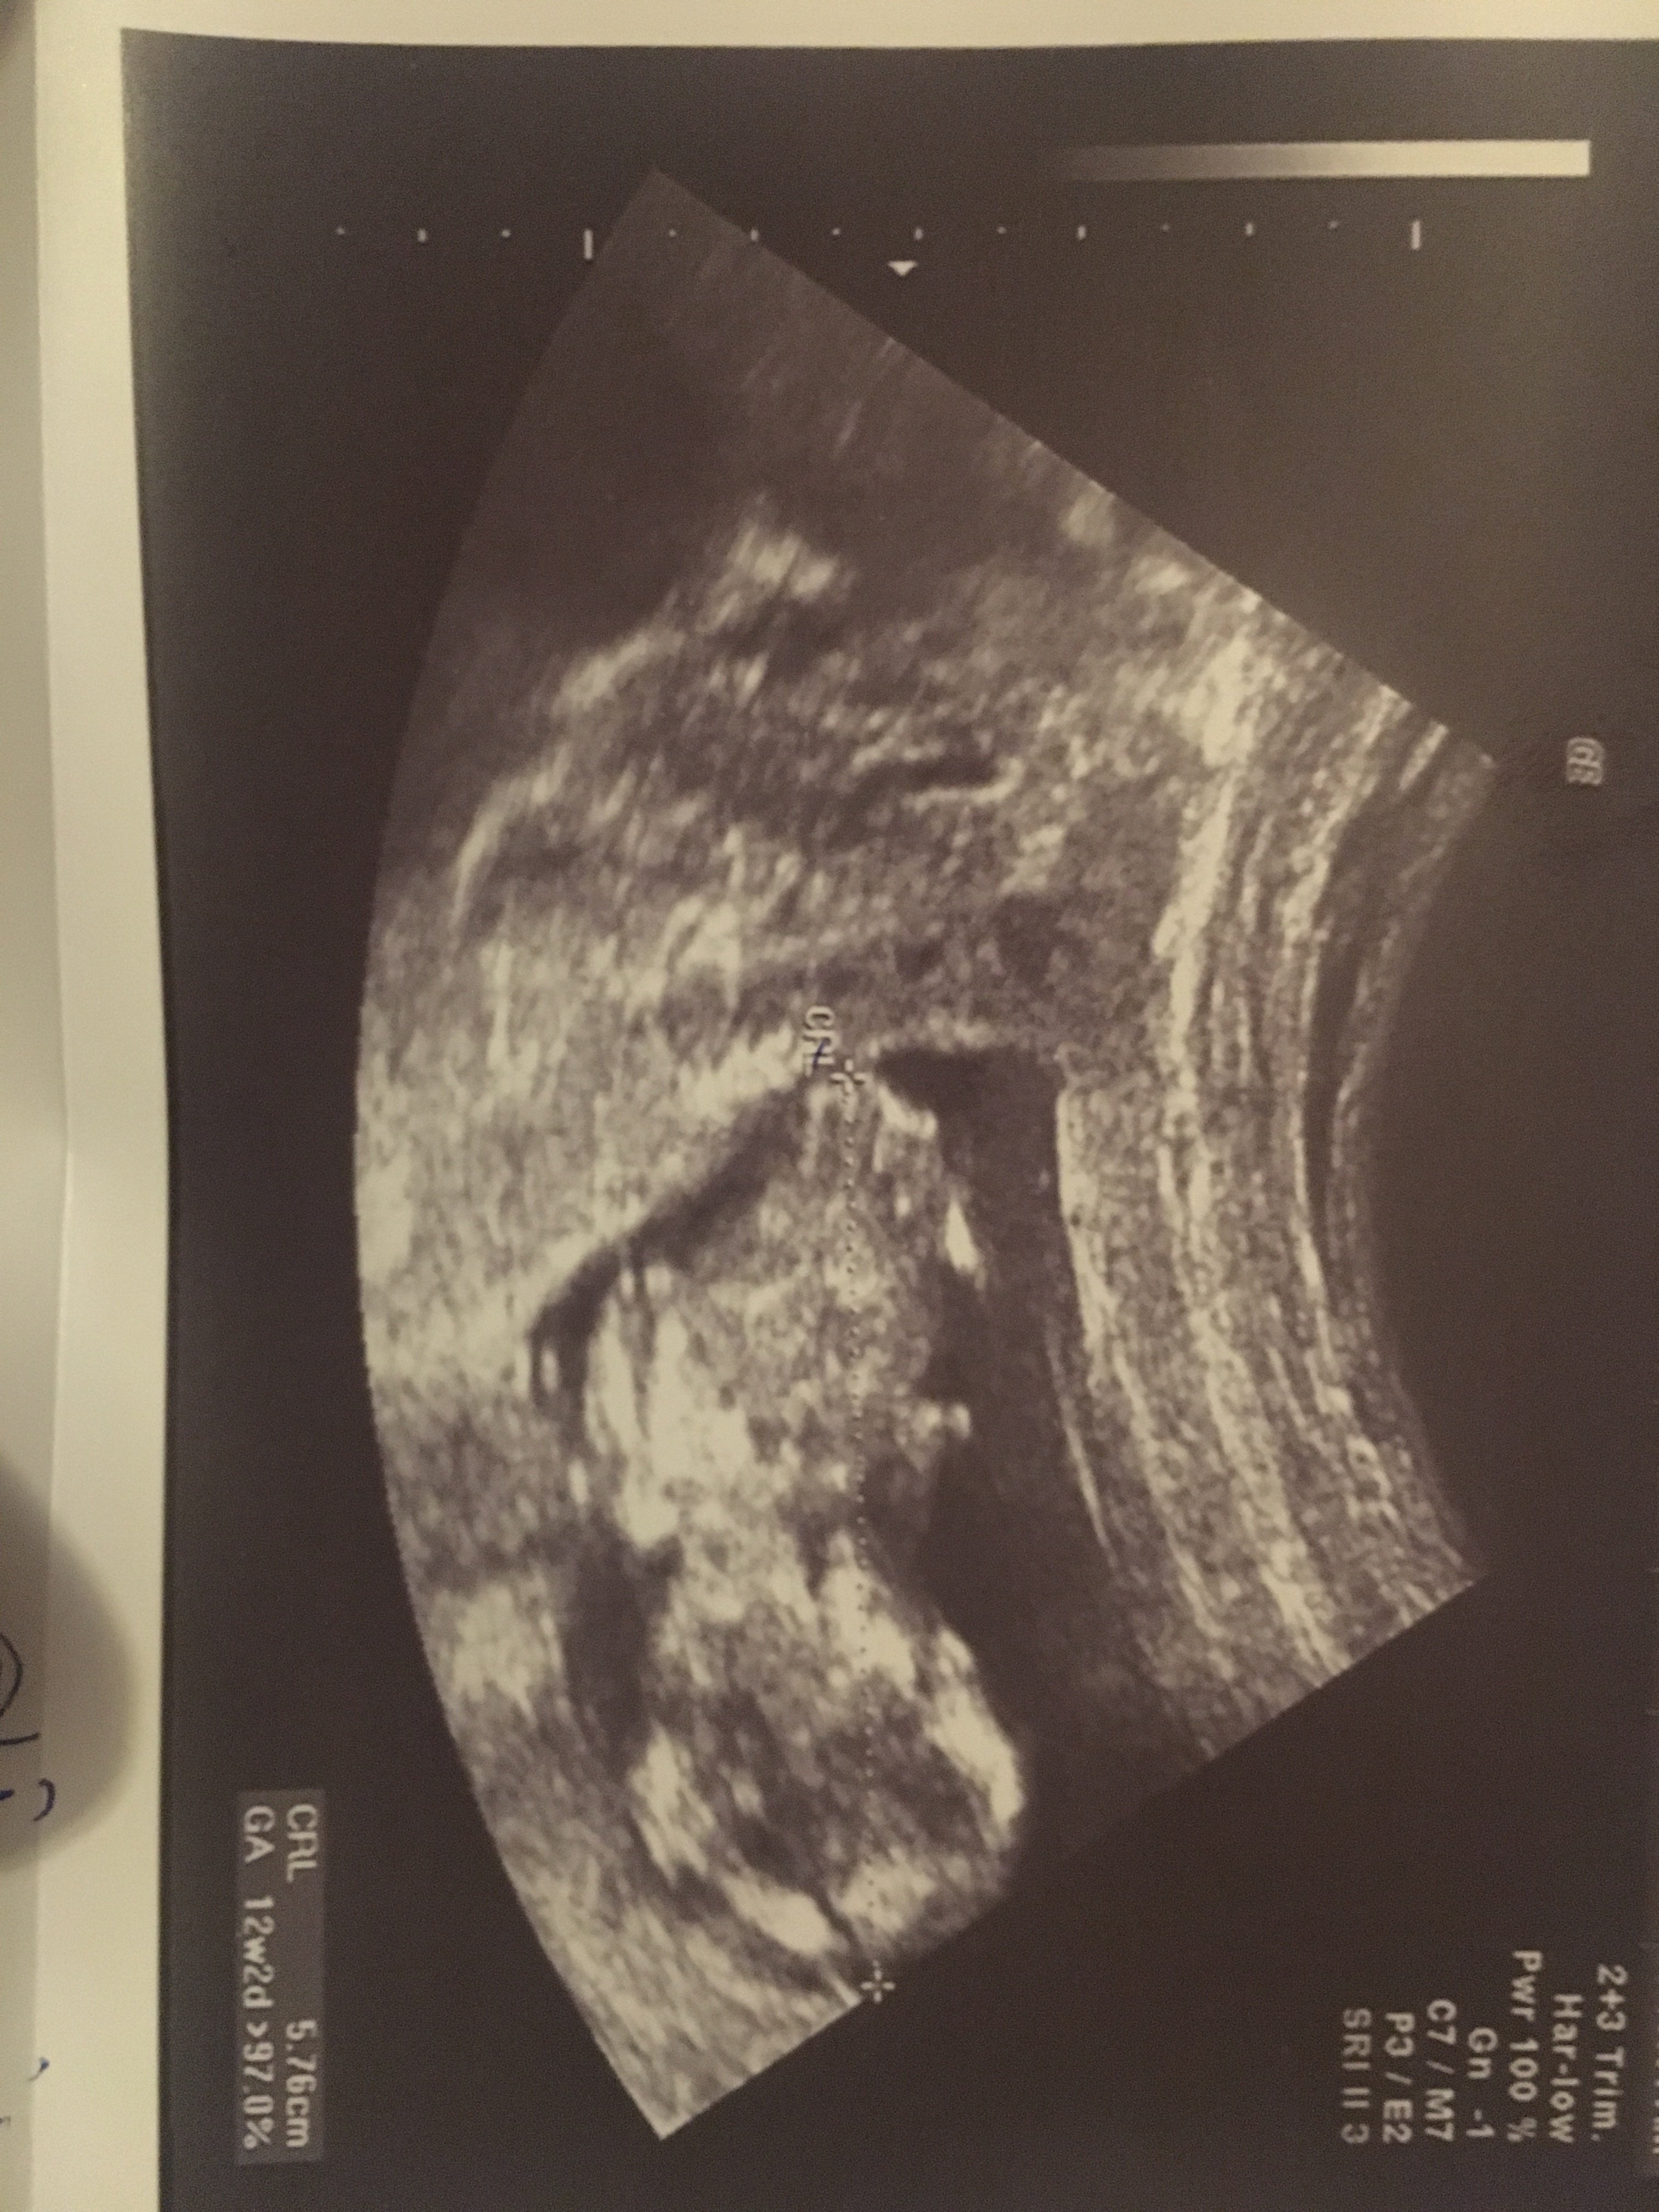

Witam w 19 tygodniu ciąży dowiedziałam się ze będę miała dziewczynkę w 20 tyg okazało się jednak , że to chłopak. Sama już nie wiem bo na jednym usg widać na pewno dziewuche a na drugim chłopca. Może to pempowina ?? Może ktoś mi pomoże rozwiązać ta zagadkę